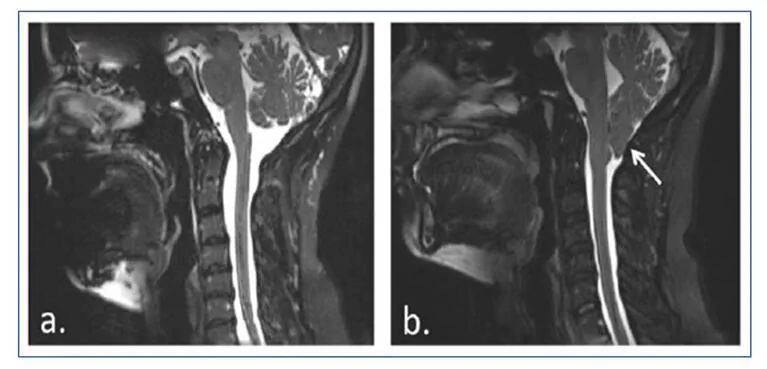

Die Malformation von Chiari Typ I beinhaltet eine kaudale Herniation der Kleinhirnmandeln von etwa 5 mm unter das Foramen magnum, die normalerweise nicht mit einem Abstieg des Hirnstamms oder des vierten Ventrikels oder mit Hydrozephalus einhergeht, wohl aber mit Syringomyelie.

Ein Mädchen mit diagnostizierter Malformation von Chiari Typ I und Syringomyelie, das im Alter von 12 Jahren operativ behandelt wurde.